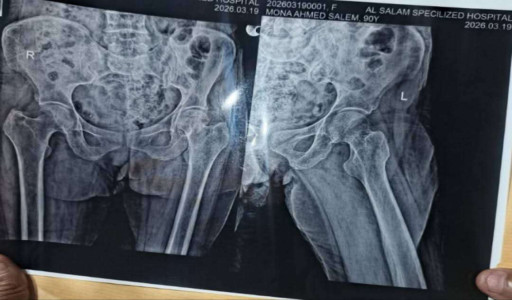

تحتاج سيدة كبيرة في السن، بعد تعرضها لسقوط أدى إلى كسر الرمانة، إلى كرسي متحرك يسهل لها التنقل اليومي.

ويبلغ سعر الكرسي المطلوب حوالي 105 آلاف ريال يمني، فيما ناشد ناشطون ومبادرات #عون_المحتاج المجتمع للتعاون والمساهمة في توفير الكرسي لتسهيل حياة السيدة وتحسين حركتها.